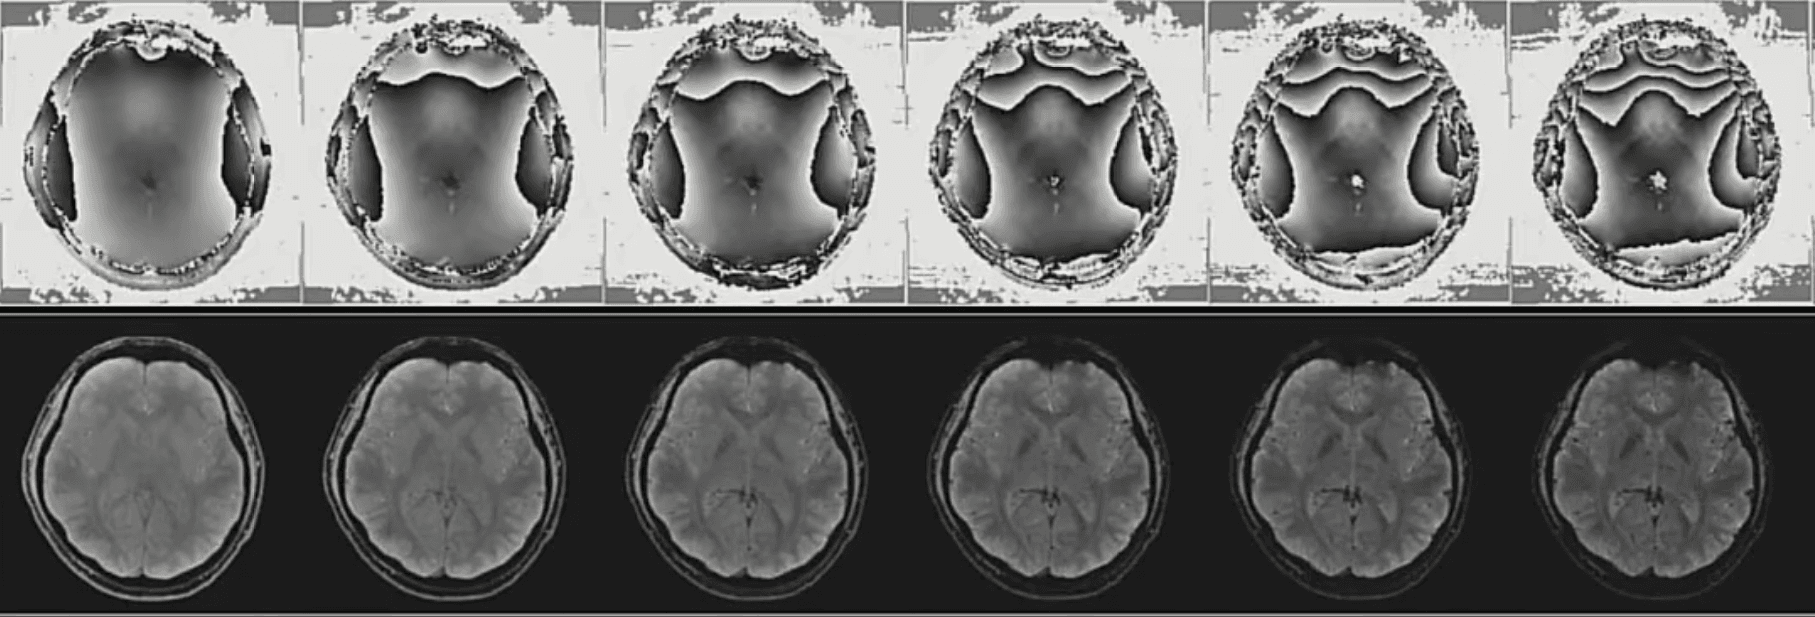

三、图像处理

磁共振图像后处理技术通过使用数字信号处理、数学变换、深度神经网络等技术对输入的磁共振图像进行处理,实现图像的增强、病灶的标记与分割。经处理图像可以为临床诊断提供可靠的依据,提高诊断准确率及诊疗效率。当前研究方向包括磁共振图像去噪,磁共振图像去伪影以及磁共振图像超分辨率。

7.png